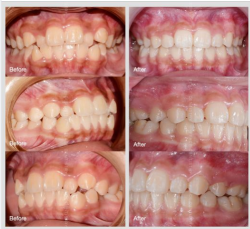

Ca lâm sàng: chỉnh nha mắc cài hoàn thành sau 20 tháng (Khách hàng nữ: 14 tuổi)

CHẨN ĐOÁN CHÍNH: ??̆?? ???? ???́? | ??̆́? ???̛?̛̣? ??? | ??̣̂?? đ?̛?̛̀?? ???̛̃?... CHỈ ĐỊNH ĐIỀU TRỊ CHÍNH: Chỉnh nha mắc cài kim loại Thời gian...